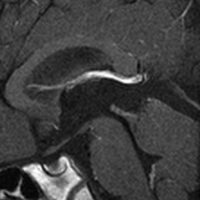

これも偶然発見された無症状の女性の小さい松果体細胞腫ですが,ほとんど実質性でのう胞がありません。右はCISSという画像です。中脳の視蓋は圧迫されて変形していますが,中脳水道がまだ閉塞していないのがよくわかります。